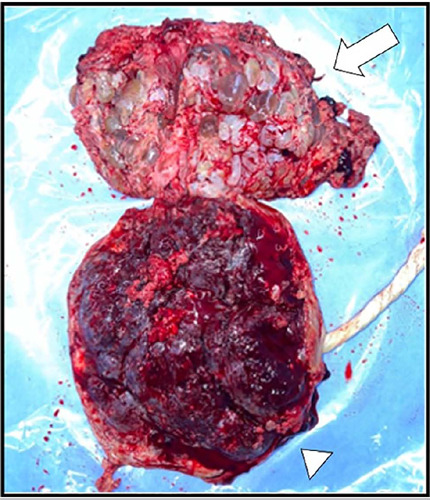

妊娠滋养细胞疾病(GTD)包括由双胎妊娠受精期间发生的遗传异常引起的异质性疾病,通常可能与辅助生殖技术有关。一种极其罕见的GTD的表现是双妊娠葡萄胎与胎儿共存,这种情况可能是母亲和胎儿并发症的重要原因。一名36岁的女性(G2, P0, A1)接受了友好的卵巢控制刺激(COS),然后进行了宫内人工授精(IUI)以辅助生殖为目的,导致双胎妊娠,最初的特征是两个妊娠囊。然而,一个囊未能发育,而是退化为磨牙滋养细胞疾病,而另一个则维持正常胎儿的正常生长。在妊娠33周时,患者出现先兆子痫,需要在三级医疗机构进行剖宫产。生殖辅助手术可能与滋养细胞疾病有关。此外,囊性病变的存在需要广泛的鉴别诊断,磁共振成像是准确评估和区分结构的有价值的工具。

Gestational trophoblastic diseases (GTD) comprise a heterogeneous group of disorders arising from genetic anomalies occurring during fertilization in twin pregnancies and often may be associated with assisted reproductive techniques. An exceedingly rare presentation of GTD is a twin pregnancy hydatidiform mole with a co-existing fetus, condition which may be an important cause of complications for the mother and the fetus. A 36-year-old woman (G2, P0, A1) underwent a friendly controlled ovarian stimulation (COS) followed by intrauterine insemination (IUI) for assisted reproductive purposes, resulting in a twin pregnancy initially characterized by two gestational sacs. However, one sac failed to progress and instead degenerated into molar trophoblastic disease, while the other sustained a normal fetus with regular growth. At 33 weeks gestation, the patient developed preeclampsia, necessitating delivery via cesarean section at a tertiary care facility. Reproductive-assisted procedures may be linked to cases of trophoblastic disease. Additionally, the presence of cystic lesions warrants a wide differential diagnosis, with magnetic resonance imaging serving as a valuable tool for accurate assessment and differentiation of structures.